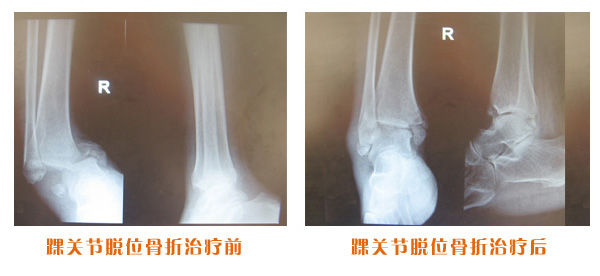

肥城市安駕莊梁氏骨科醫(yī)院是一所以梁氏手法正骨配合膏藥為特色的現(xiàn)代化專科醫(yī)院。

梁氏骨科術始創(chuàng)于清雍正年間,歷經(jīng)八代,至今已有三百年歷史。據(jù)1929年泰安縣志載“梁瑞圖先生,字增生,號蓮峰,安駕莊人,精岐黃并發(fā)明接骨,凡跌打車凡跌打車軋皮不破而碎骨者......【詳細】 |